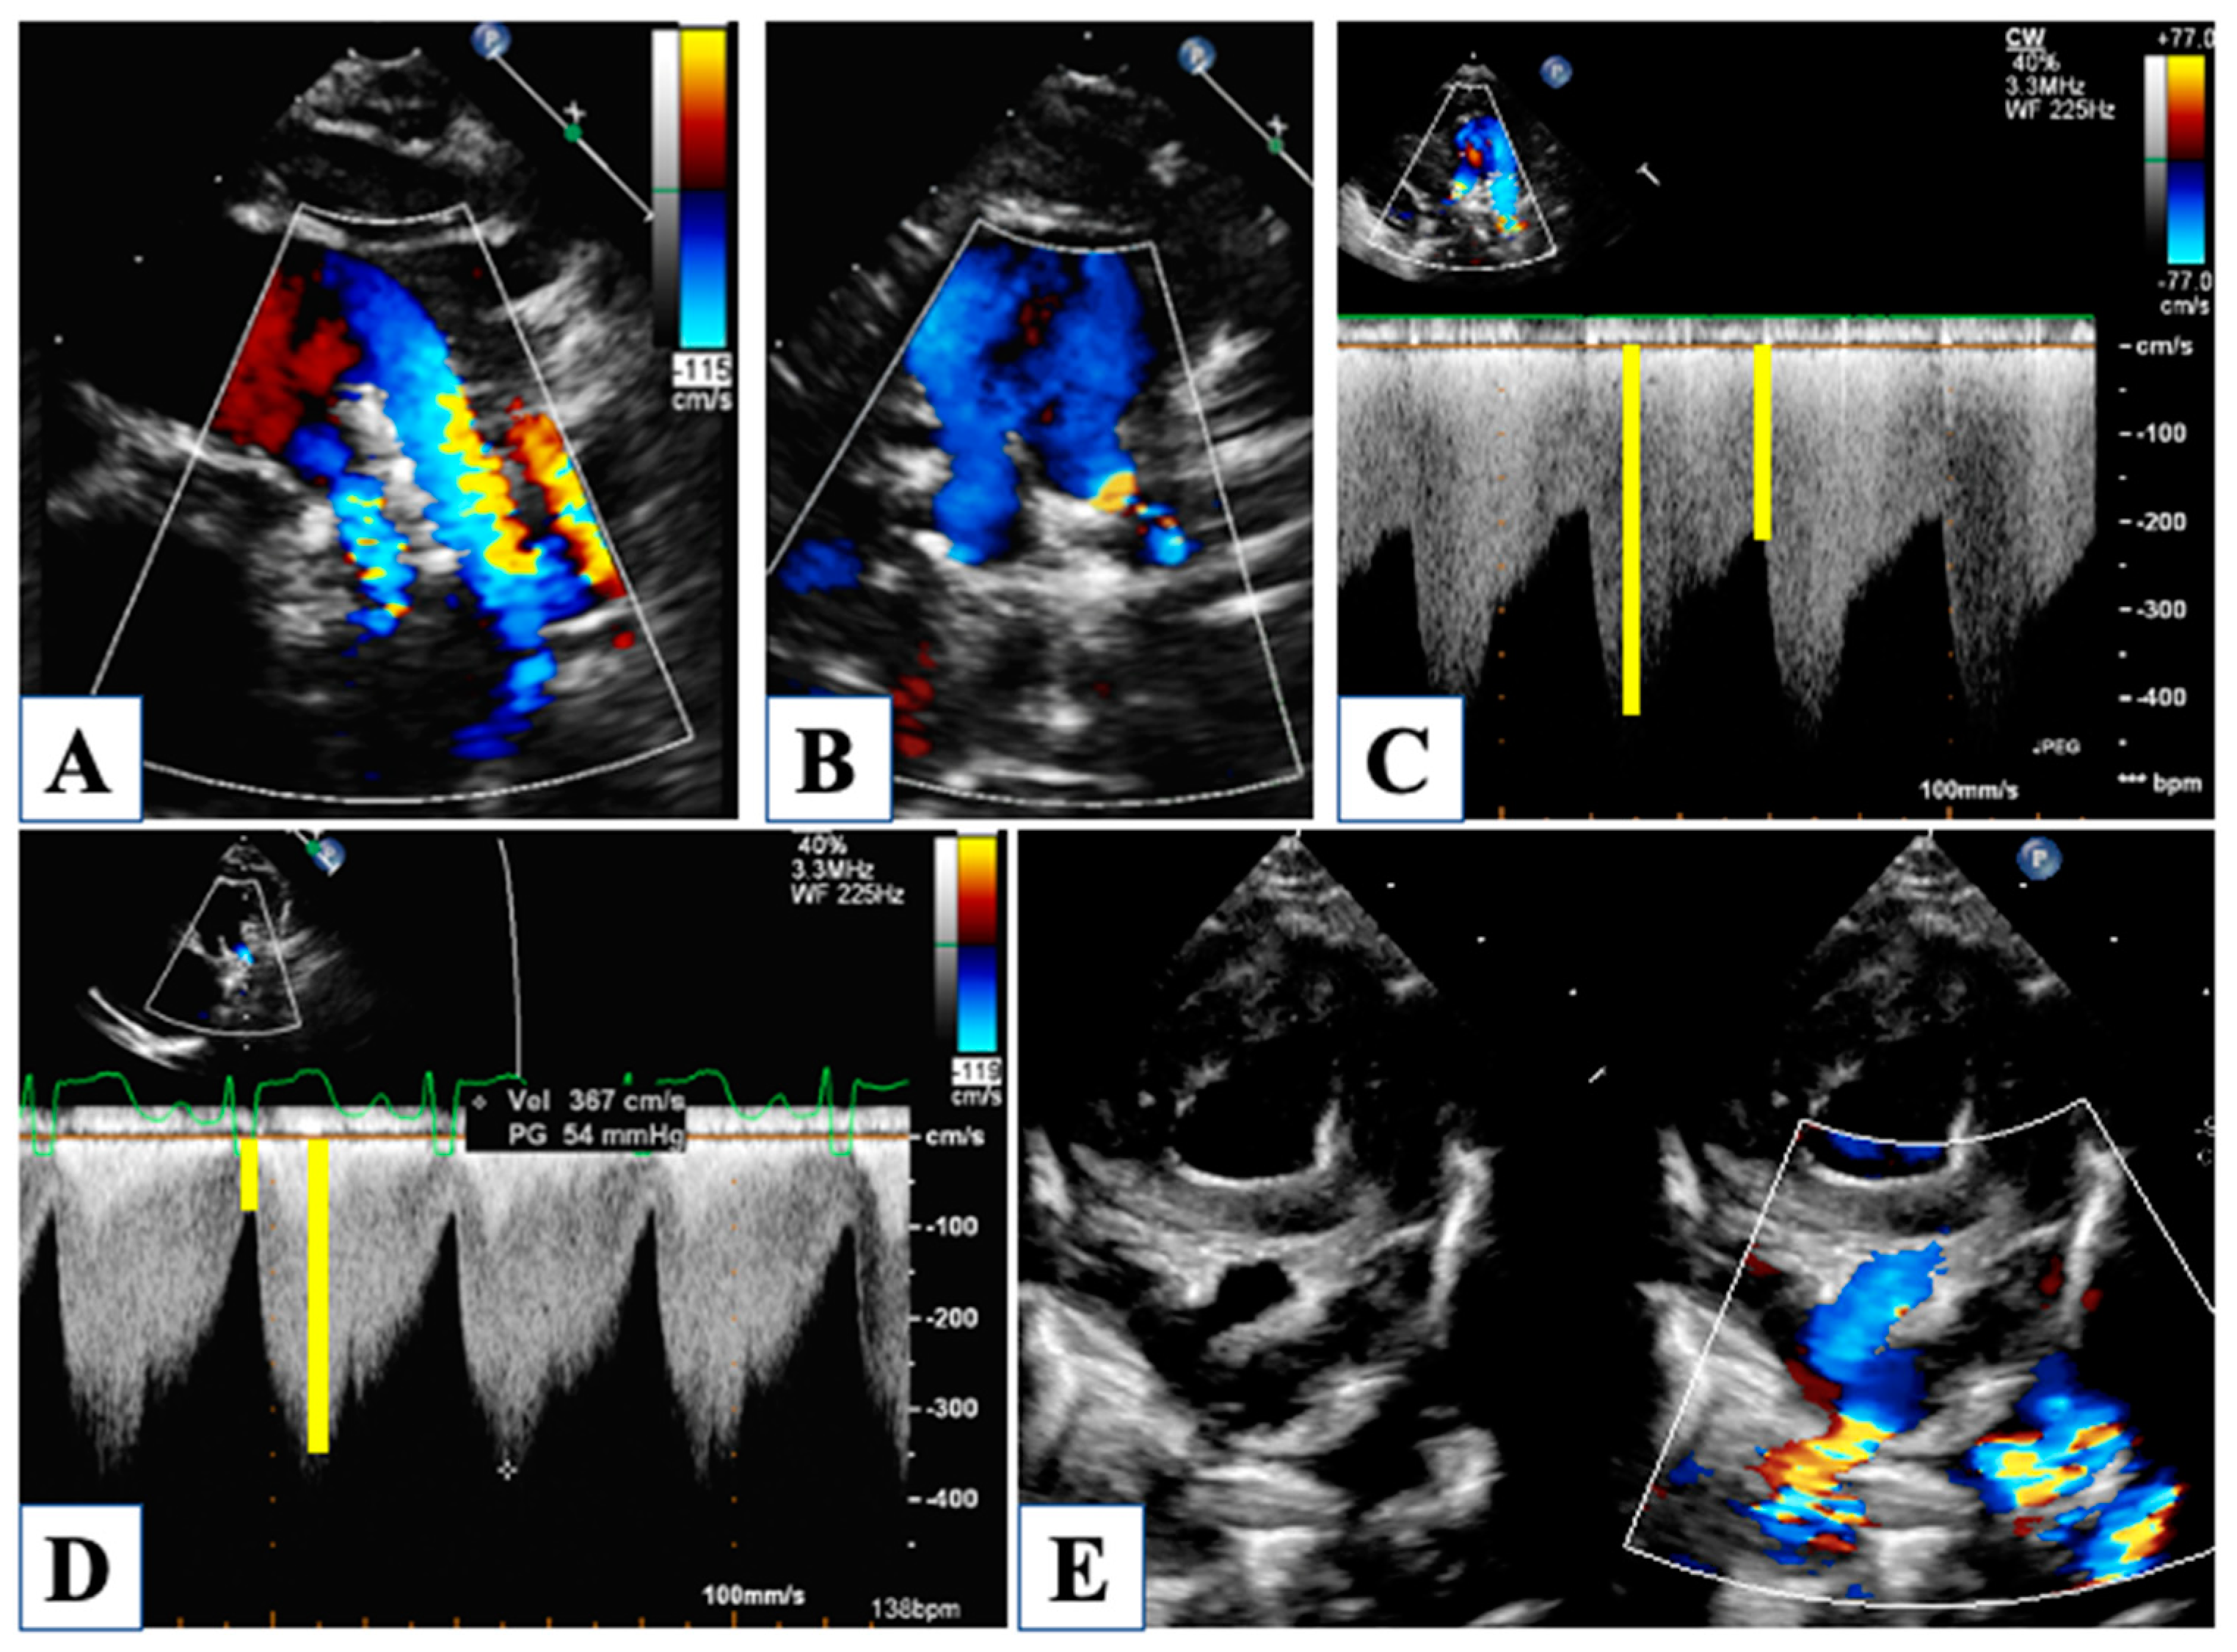

| Friedberg et al., 2007 | [10] | All | S/D duration ratio | Tricuspid regurgitation jet | High S/D ratio correlated with worse RV function |

| Carrillo et al., 2021 | [11] | All | RVFAC, TAPSE, Tricuspid regurgitation | RV area change, annular excursion, tricuspid regurgitation jet (vena contracta) | Impact on survival at all stages |

| Petko et al., 2011 | [12] | After stage I | RVFAC, TAPSE, Tricuspid regurgitation | RV area change, annular excursion, tricuspid regurgitation jet (vena contracta) | Impact on survival at all stages |

| Bellsham-Revell et al., 2012 | [13] | All stages (Norwood) | TDI indices, Myocardial performance index, S/D duration ratio | TDI of the RV free wall, tricuspid regurgitation jet | Myocardial performance index increased compared to normal values. |